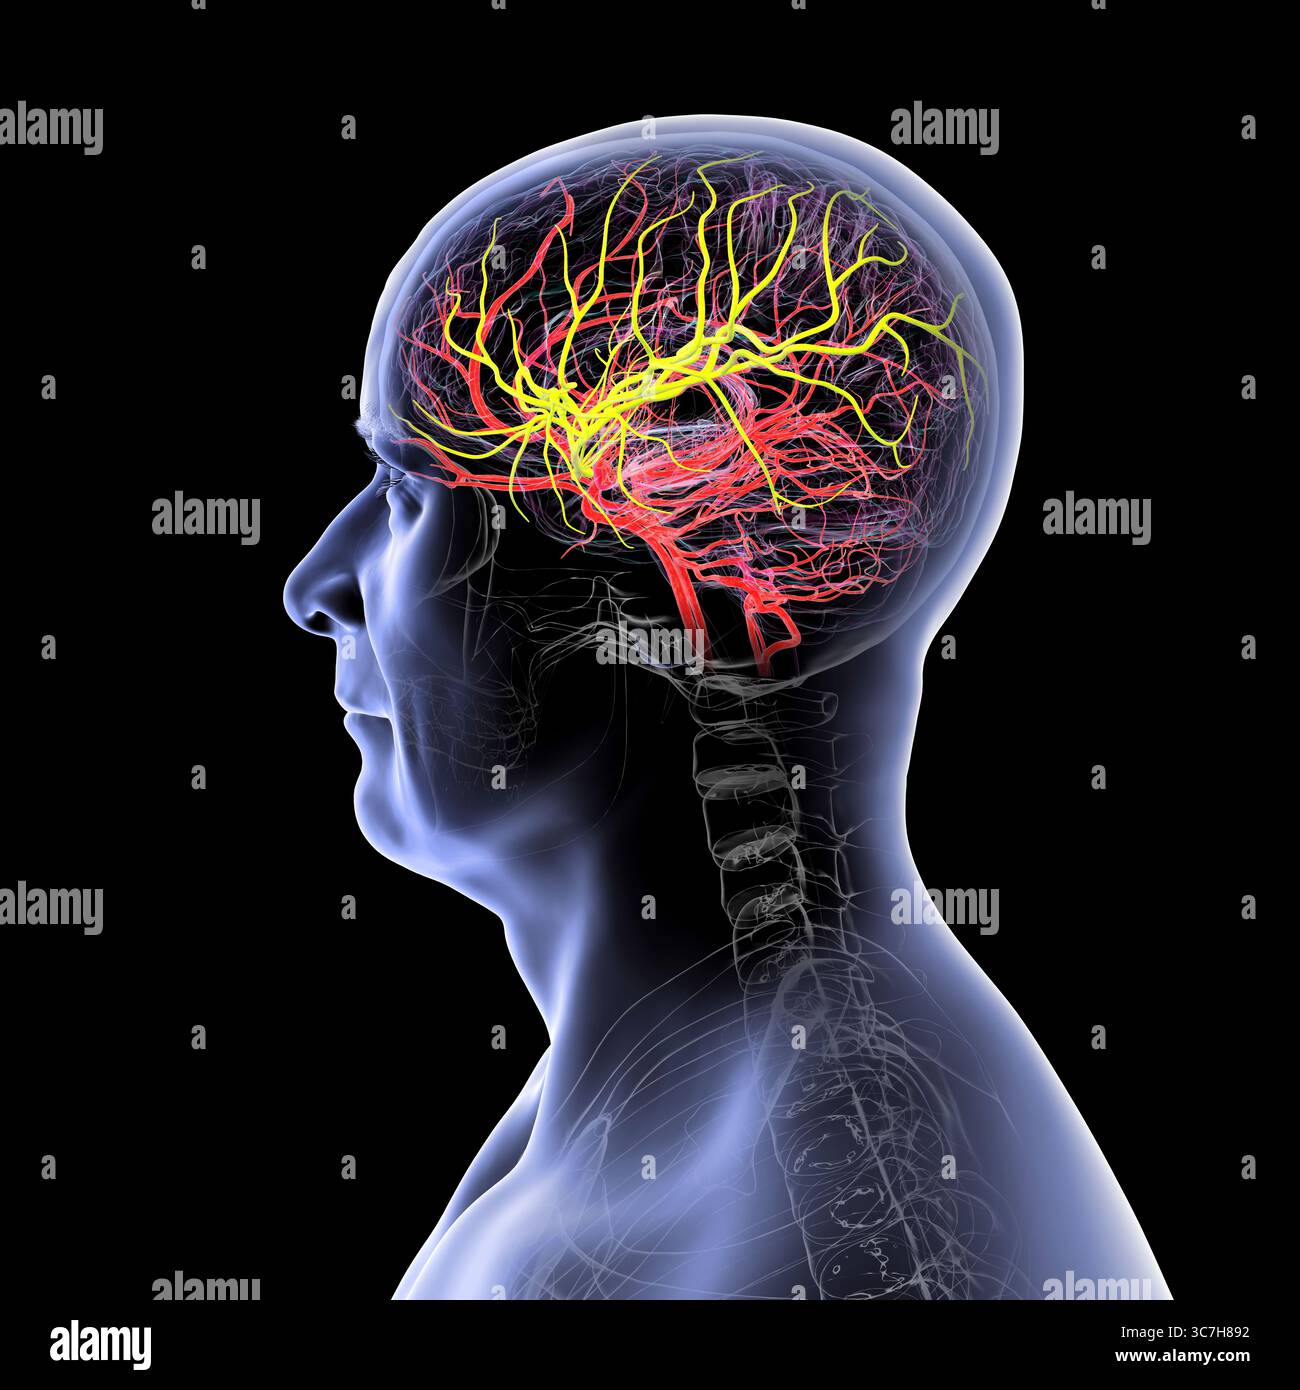

RFGMTM2D–Gehirn-System und Blut Gefäßversorgung. Grafik zeigt das Gehirn mit Arterien (rot) und Venen (blau).

RFR3P9KW–Illustration der Blutversorgung des Gehirns. Das Gehirn hat wenig Kapazität, Nährstoffe zu speichern, aber es braucht eine hohe Versorgung mit Sauerstoff und Glukose.

RFGMTM21–Gehirn-System und Blut Gefäßversorgung. Grafik zeigt das Gehirn mit den richtigen Großhirn entfernt und Arterien (rot) und Venen (blau).

RFR3P9KC–Illustration der Blutversorgung des Gehirns. Das Gehirn hat wenig Kapazität, Nährstoffe zu speichern, und benötigt eine hohe Versorgung mit Sauerstoff und Glukose.

RF3C7H8AB–Darstellung der arteriellen Blutversorgung des Gehirns mit hervorgehobener Arteria cerebri Media (gelb), die Blut zu den frontalen, temporalen und parietalen Lappen liefert, entscheidend für die Gehirnfunktion.

RF2SGJF64–Anatomisches Diagramm der zerebralen Durchblutung. Sie ist für die Aufrechterhaltung der Gehirnfunktionen und für die Versorgung mit Sauerstoff und Nährstoffen von entscheidender Bedeutung.

RF3C7H897–Darstellung der arteriellen Blutversorgung des Gehirns mit hervorgehobener Arteria cerebri Media (gelb), die Blut zu den frontalen, temporalen und parietalen Lappen liefert, entscheidend für die Gehirnfunktion.

RF2SGJF65–Anatomische Darstellung der zerebralen Durchblutung. Das Blut gelangt durch die Arterien der Karotis und der Wirbelsäule in das Gehirn und liefert Sauerstoff und Nährstoffe.

RF3C7H892–Darstellung der arteriellen Blutversorgung des Gehirns mit hervorgehobener Arteria cerebri Media (gelb), die Blut zu den frontalen, temporalen und parietalen Lappen liefert, entscheidend für die Gehirnfunktion.

RF3C7H890–Darstellung der arteriellen Blutversorgung des Gehirns mit hervorgehobener Arteria cerebri Media (gelb), die Blut zu den frontalen, temporalen und parietalen Lappen liefert, entscheidend für die Gehirnfunktion.